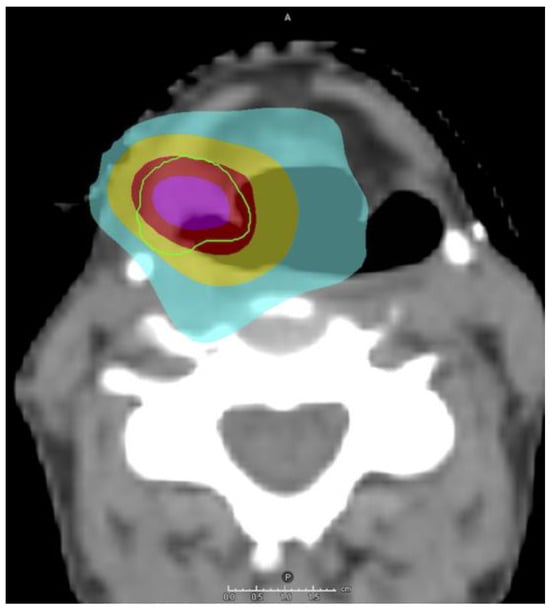

3.2. Enhancing Tumor Control

3.3. IMRT vs. Brachytherapy